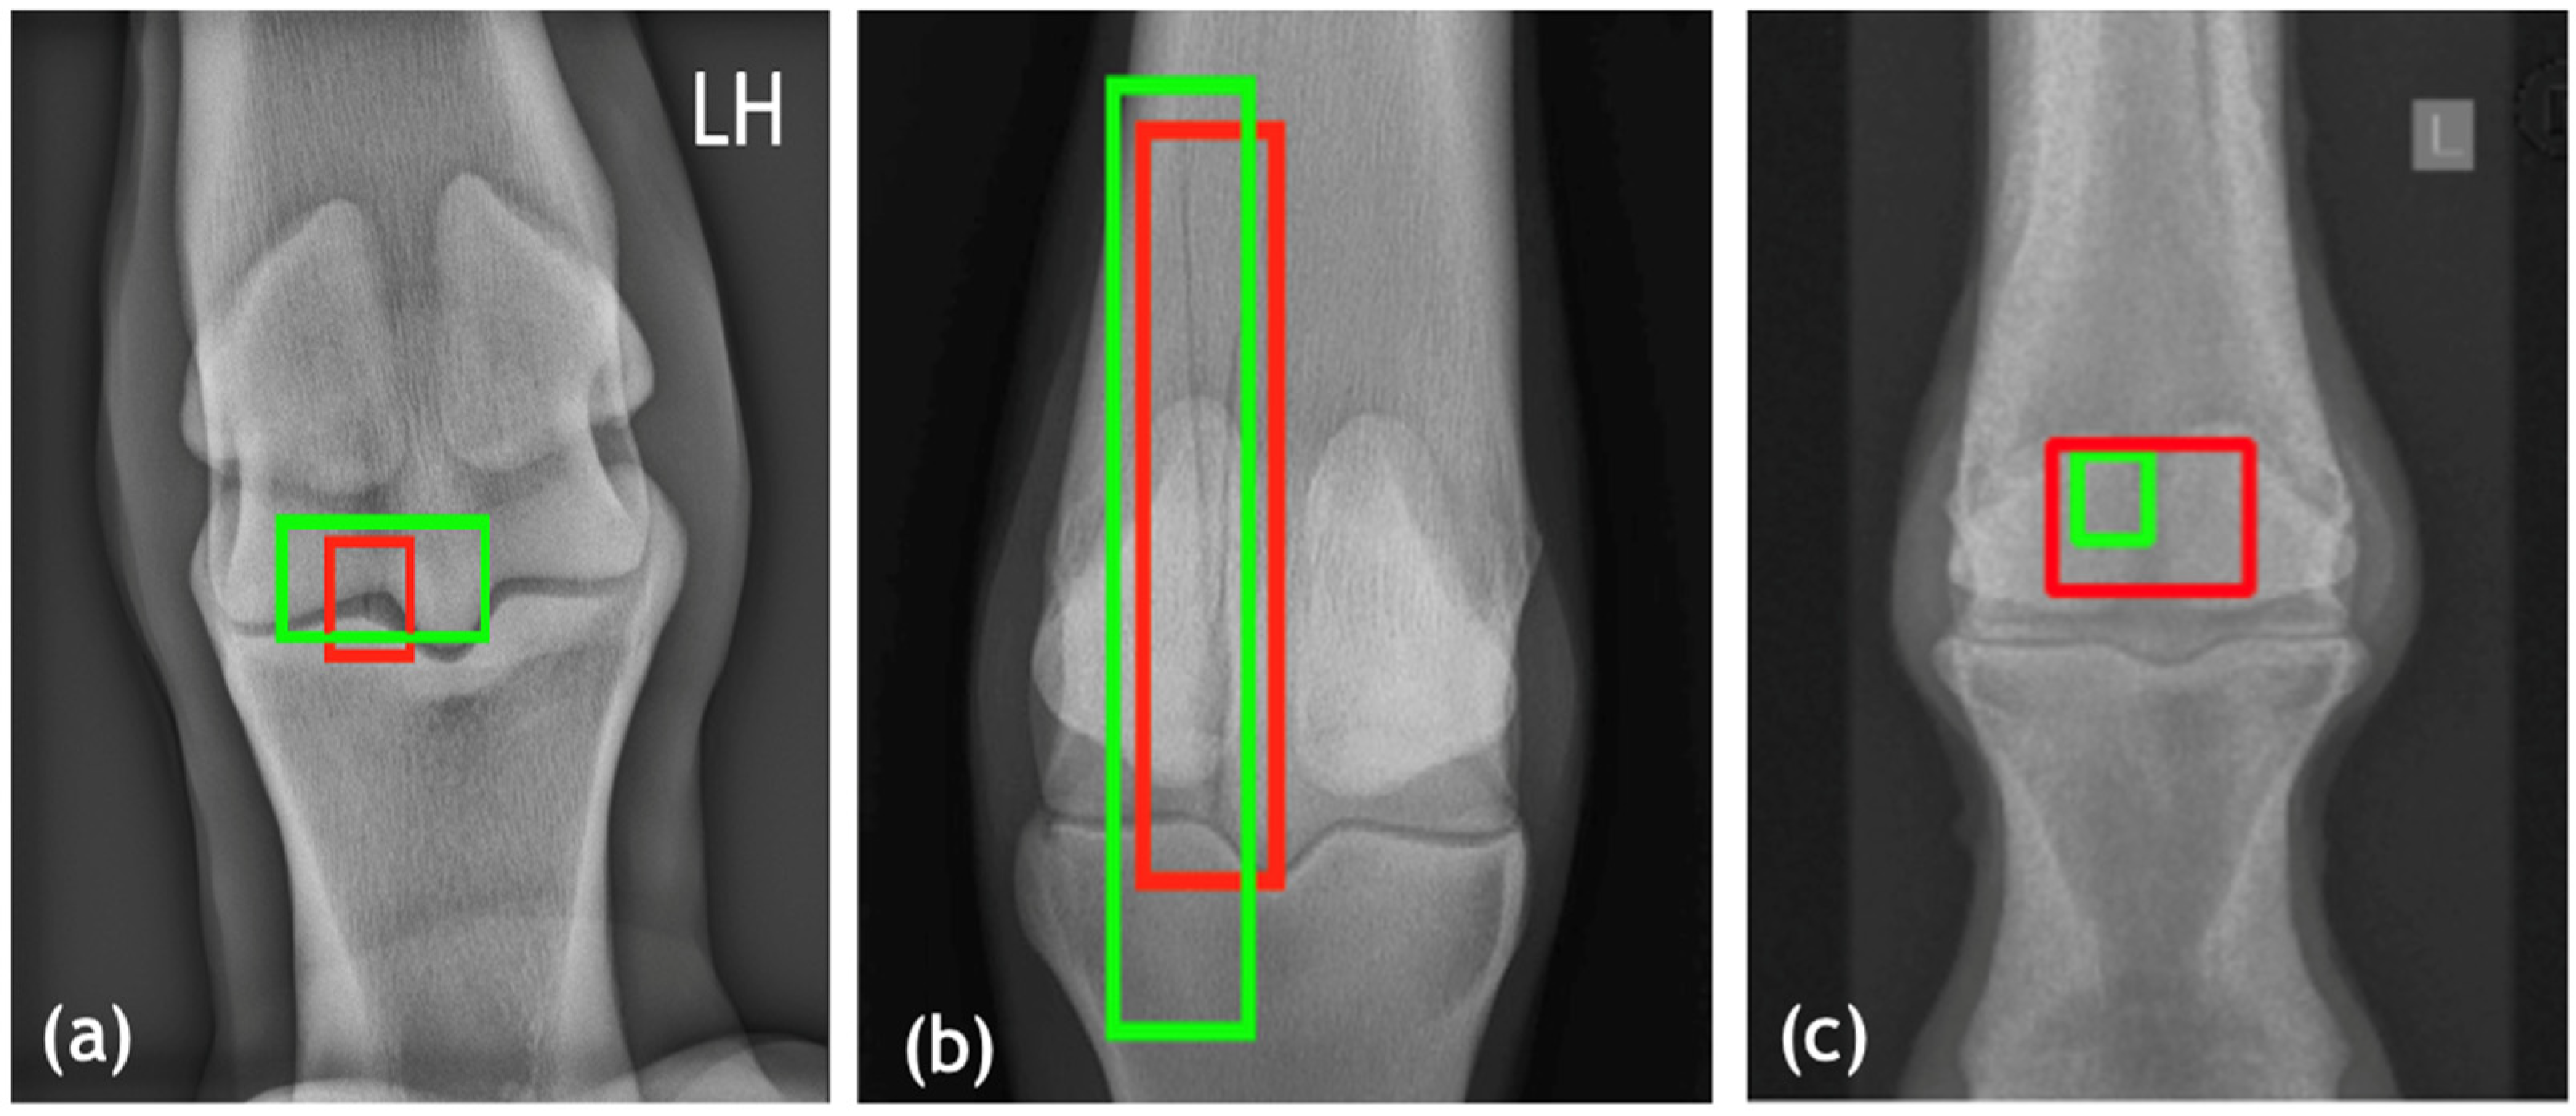

Prior to fine-tuning using equine images, fracture detection had below 50% accuracy at the image (patch) level on equine datasets, reflecting limited generalization from the initial training phase (pretrained model). After fine-tuning using equine images, the final model achieved high detection accuracy and demonstrated robust generalization across image orientations and scanner types. Performance remained stable when applied to post-operative images containing implants (Figure 3), suggesting resilience to metal artifacts and anatomical distortions. The incorporation of an IoU-based loss function penalizing poor spatial overlap contributed significantly to bounding box precision, which is essential for clinical interpretability. Furthermore, the model’s inference time per image was under 0.5 s on an A100 GPU, making it suitable for real-time triage in clinical settings or batch analysis of hospital archives.

Figure 3. Visual validation of fracture detection in post-operative equine dataset for dorsopalmar (DP) projections. Predicted bounding boxes (green) are compared with ground truth annotations (red).